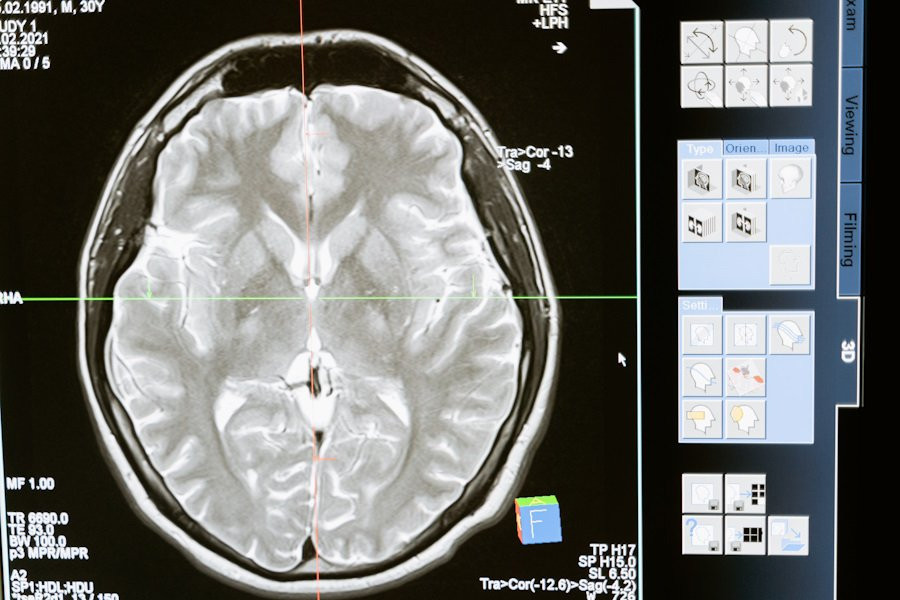

ТАСС: неврологи называют факторы, убивающие мозг

Головной мозг, наша самая сложная "компьютерная" система, подвержен воздействию многих факторов, и его работа остается загадкой. В нем содержится около 100 млрд нейронов, каждый из которых связан с другими посредством синапсов, создавая замысловатую паутину. Мозг способен выполнять операции со скоростью от 1012 до 1028 FLOPS/сек, в то время как самый быстрый суперкомпьютер 2022 года работает с мощностью 1,6 Х 1018 FLOPS/сек, сообщает ТАСС.

По данным неврологов, мозг чувствителен к воздействию различных факторов, включая алкоголь и курение, но наиболее вредными являются дефицит кислорода и глюкозы в крови. Нейроны в мозгу зависят от поступления глюкозы через кровь, и при отсутствии кровообращения они начинают умирать в течение пяти минут. Стресс также влияет на мозг, меняя химический баланс и передачу сигналов.